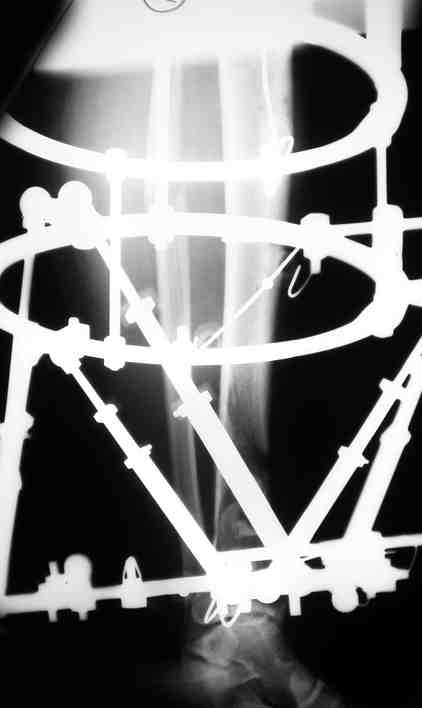

Выше приведены рентгенограммы 13-летнего подростка, страдающего от огнестрельного многооскольчатого перелома дистальной трети бедра. AO наружный фиксатор наложенный в день травмы не дал приемлемой редукции. Через три недели после перелома аппарат Илизарова был наложен без попытки одномоментной репозиции на операционном столе.

There are X-Rays of a thirteen year old boy with a comminuted distal femur fracture secondary to a gunshot wound, initially treated with an AO external fixator. The alignment was unacceptable and an Ilizarov external fixator was applied three weeks after the injury. No attempt of definitive reduction was made during the surgery.

Гексаподная приставки наложена на 10 дней и приемлемая редукция была получена.

The Hexapod set was applied for ten days and acceptable reduction was received.

По окончанию редукции Гексаподный сет был снят и дальнейшее ведение больного проходило в стандартном режиме аппарата Илизарова. Хороший анатомо-функциональный результат был получен.

When reduction was finished, the Hexapod set was removed and further management has been continued by standard Ilizarov regime. Good anatomic and functional results were achieved.